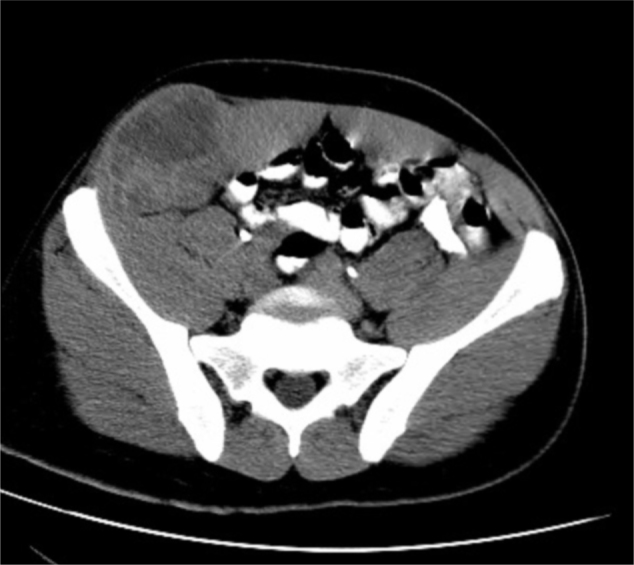

Figure 1C.

43-year-old man with metastatic synovial sarcoma of the abdominal wall. Axial CT of abdomen with oral but not intravenous contrast shows mixed density soft tissue mass arising within the right external oblique muscle. There is no invasion into the abdominal cavity.

Figure 1D.

43-year-old man with metastatic synovial sarcoma of the abdominal wall. Post-contrast CT shows a nodular, non-homogeneous pattern of enhancement.